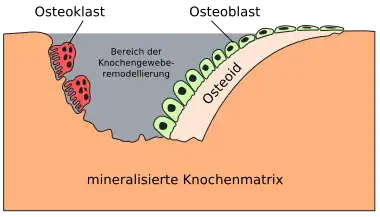

Im Laufe des Remodelings „graben“ sich Osteoklasten mit Hilfe verschiedener lytischer Enzyme (Cathepsin K, MMP-3 und 9, ALP) in die Knochenmatrix und bilden Gruben an der Oberfläche der Trabekel (Howshipsche Lakunen) oder Bohrkanäle im Inneren der Kortikalis. Dieser Knochenresorption[3] nachfolgend sezernieren Osteoblasten in großen Feldern von wenigstens 50 Zellen neues kollagenes Knochengrundgerüst (Osteoid) ab, welches im weiteren Verlauf nach und nach kalzifiziert und somit neue Knochenmatrix bildet. Einige der Osteoblasten werden hierbei von der mineralisierenden Matrix eingeschlossen und differenzieren im weiteren Verlauf zu Osteozyten.

-